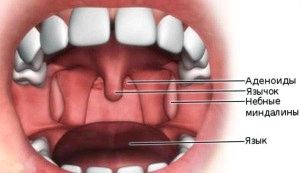

Тонзиліт - запальний процес, який має інфекційно-алергічну природу і вражає лімфоїдну тканину мигдаликів дитини.

- Почервонілі і набряклі мигдалини, в деяких випадках з гнойничками,